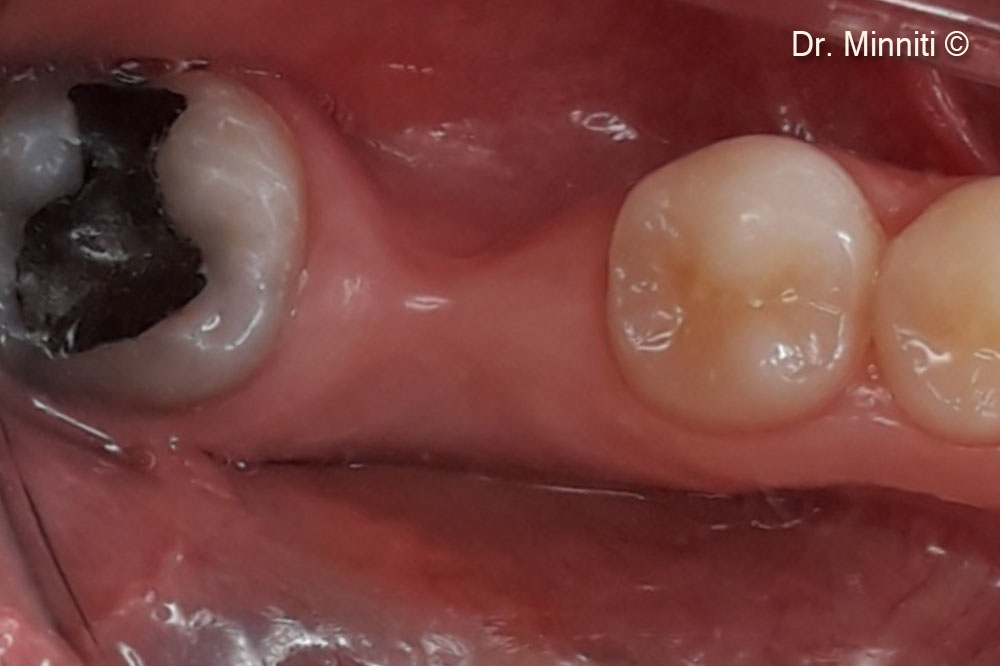

Tình hình ban đầu

Một bệnh nhân nữ (37 tuổi) có biểu hiện teo mô mềm nghiêm trọng theo chiều ngang và chiều dọc.

Một bệnh nhân nữ (37 tuổi) có biểu hiện teo mô mềm nghiêm trọng theo chiều ngang và chiều dọc.